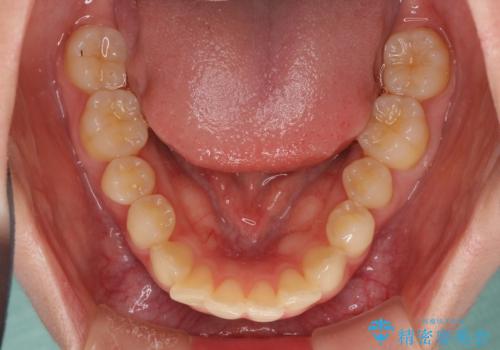

- 前歯2本が飛び出してることを気にして来院された患者様です。

全体的に黄ばんだ歯の色も気になるとのことで、マウスピース矯正により飛び出した前歯を治しつつ、ホームホワイトニングを併用して黄ばみを解消していくこととしました。

歯と歯の間を削ることで、飛び出した前歯が引っ込み、スッキリとした口元となりました。

歯の黄ばみも改善され、明るい歯並びとなりました。